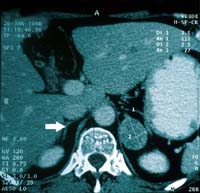

รูปที่ 13 แสดง Pheochromocytoma ในผู้ป่วยหญิงอายุ 42 ปี

รูป B. ภาพ MRI T2 ระนาบ coronal แสดงก้อนใหญ่ตะปุ่มตะป่ำข้างขวา และก้อนเล็กข้างซ้าย ซึ่ง singal intensity ไม่เท่ากัน

(M = adrenal mass, RK = right kidney, LK = left kidney)

รูป C. ภาพ MRI T1 ระนาบตัดขวางหลังการฉีด Gd-DTPA แสดง enhancement ขาวมากในก้อนใหญ่ส่วนบนของต่อมหมวกไตข้างขวา